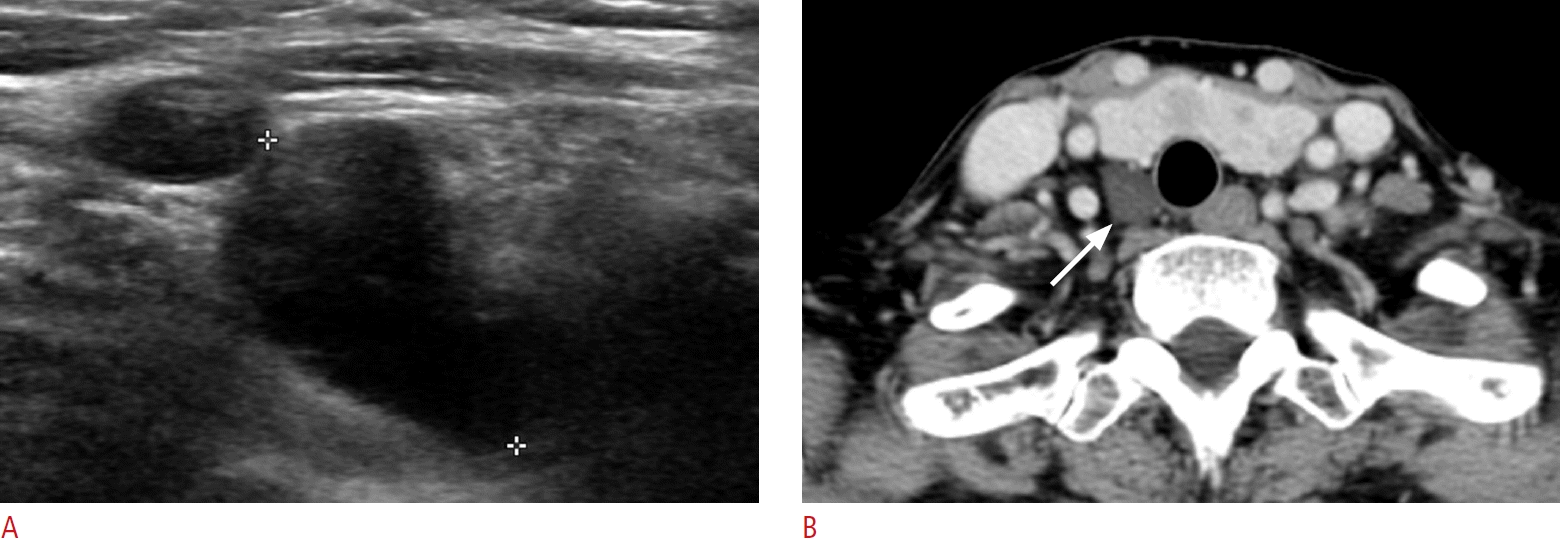

3. Kwak JY, Kim EK, Moon HJ, Kim MJ, Ahn SS, Son EJ, et al. Parathyroid incidentalomas detected on routine ultrasound-directed fine-needle aspiration biopsy in patients referred for thyroid nodules and the role of parathyroid hormone analysis in the samples. Thyroid. 2009; 19:743–748.

5. Lee B, Chung SR, Choi YJ, Sung TY, Song DE, Kim TY, et al. Diagnosis of parathyroid incidentaloma detected on thyroid ultrasonography: the role of fine-needle aspiration cytology and washout parathyroid hormone measurements. Ultrasonography. 2023; 42:129–135.

84. Ghervan C, Silaghi A, Nemes C. Parathyroid incidentaloma detected during thyroid sonography - prevalence and significance beyond images. Med Ultrason. 2012; 14:187–191.